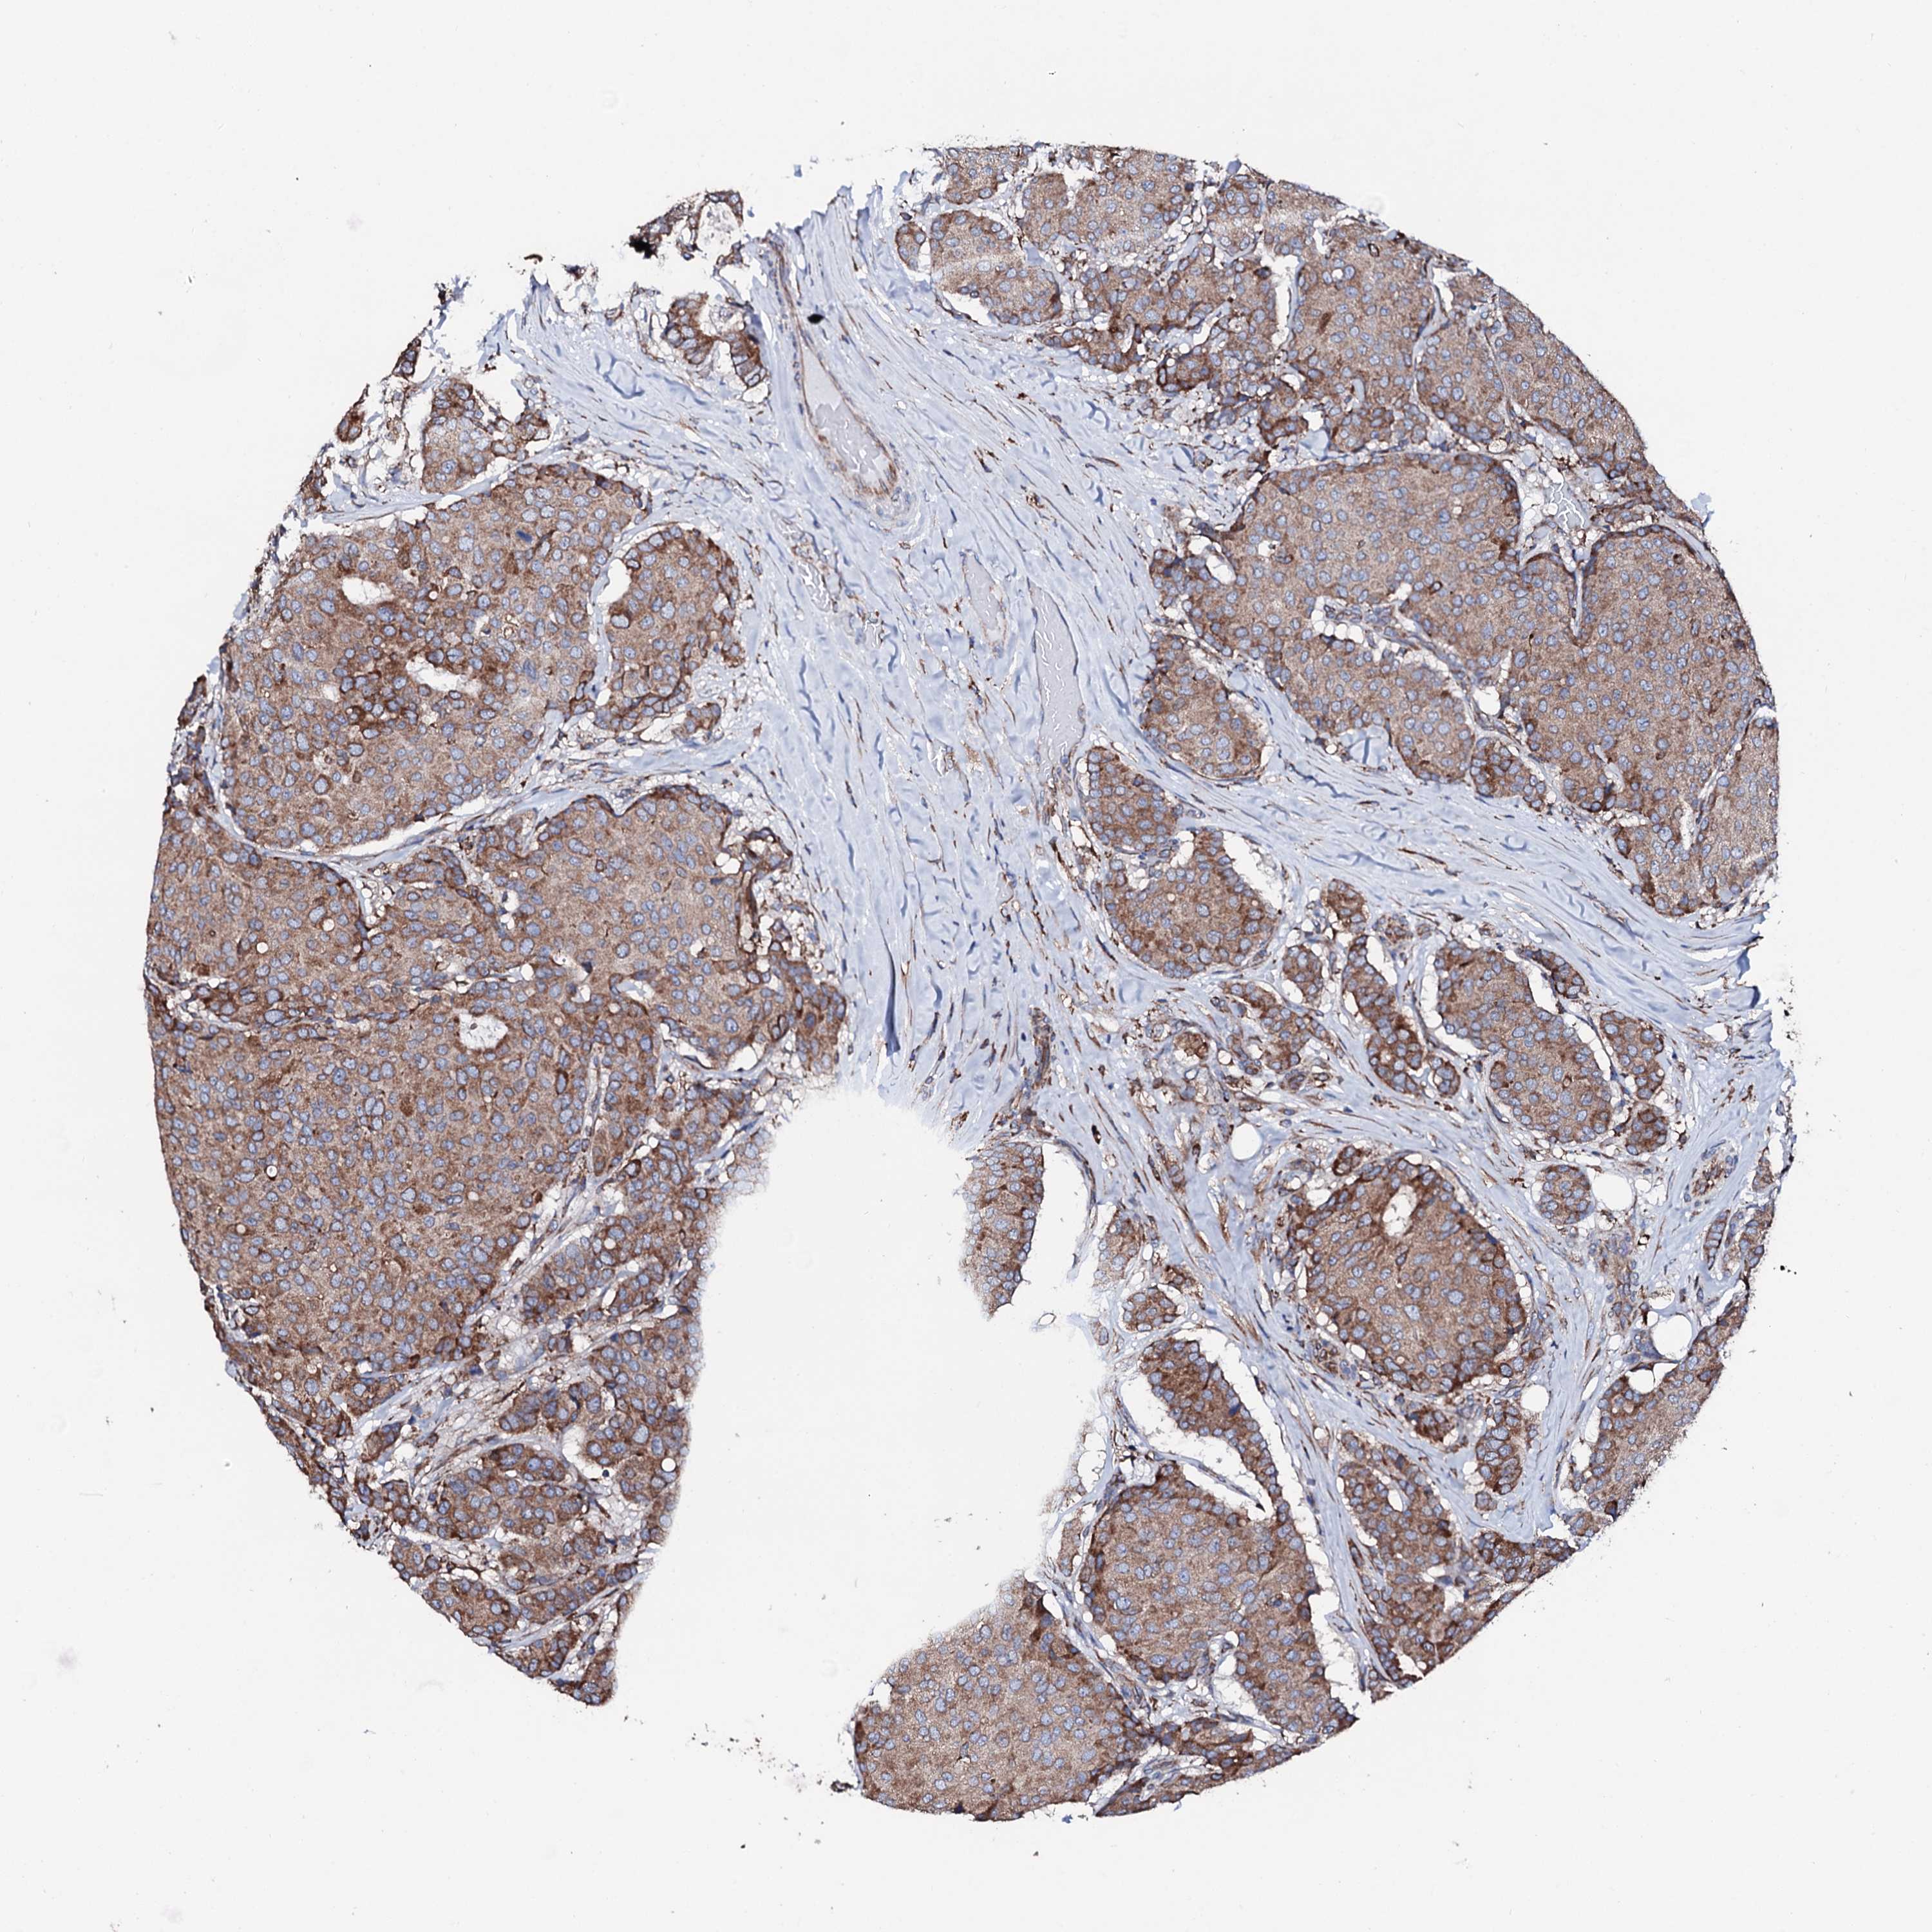

CANCER BREAST CANCER Show tissue menu

BRCA TCGA BRCA VALIDATION PROTEIN EXPRESSION